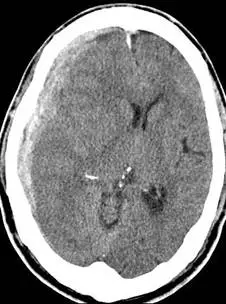

一位 68 歲男性因跌倒送來急診,意識狀態模糊,對痛刺激眼睛會張開,且左手會撥開痛刺激,但不會出聲,頭部電腦斷層如 下圖所示,下列何者正確?

頭部非增強電腦斷層(noncontrast CT)呈現右側大腦半球表面一新月形(crescent-shaped)高密度(hyperdense)血液積聚,沿著顱骨內板呈凹面朝向腦實質的形態,可跨越顱骨縫合線延伸。此影像特徵符合**急性硬腦膜下血腫(acute subdural hematoma)**的典型表現。與硬腦膜外血腫(epidural hematoma, EDH)不同,SDH 呈新月形而非雙凸透鏡形(biconvex/lenticular shape),且不受顱縫限制。右側大腦半球有輕度受壓,但中線偏移不十分顯著。

(A) 出血位置位於硬腦膜下 ✅ 正確

CT 影像顯示右側大腦表面新月形高密度影,位於硬腦膜(dura mater)與蛛網膜(arachnoid)之間,即硬腦膜下腔(subdural space)。此為本題正確答案。急性 SDH 在 CT 上呈現高密度(hyperdense)新月形病灶,可跨越顱縫延伸,為 SDH 與 EDH 的重要鑑別點。